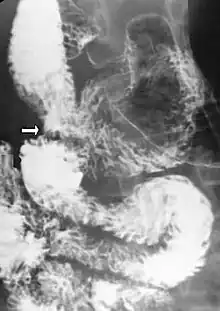

- Upper gastrointestinal series showing extreme duodenal dilation (white arrow) abruptly preceding constriction by the SMA.

Diagnosis is very difficult, and usually one of exclusion. SMA syndrome is thus considered only after patients have undergone an extensive evaluation of their gastrointestinal tract including upper endoscopy, and evaluation for various malabsorptive, ulcerative and inflammatory intestinal conditions with a higher diagnostic frequency. Diagnosis may follow X-ray examination revealing duodenal dilation followed by abrupt constriction proximal to the overlying SMA, as well as a delay in transit of four to six hours through the gastroduodenal region. Standard diagnostic exams include abdominal and pelvic computed tomography (CT) scan with oral and IV contrast, upper gastrointestinal series (UGI), and, for equivocal cases, hypotonic duodenography. In addition, vascular imaging studies such as ultrasound and contrast angiography may be used to indicate increased bloodflow velocity through the SMA or a narrowed SMA angle.[14][15]